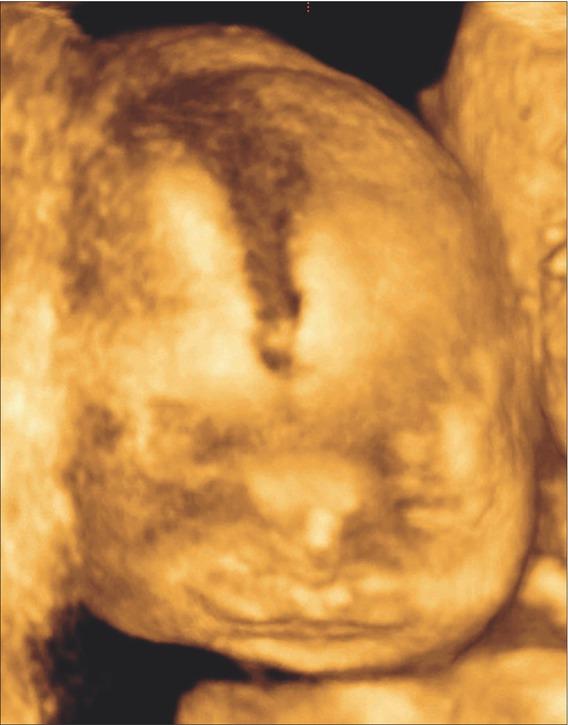

Case 2. The subsequent (third) pregnancy of the couple was uneventful during the first trimester. Ultrasound examination at 22 weeks of gestation, showed normal fetal growth, however, broad nasal bridge, micrognathia and low set ears were detected (Figures 1 and 2). Fetal fingers were also broadly spaced with abducted thumb and possible agenesis of some metacarpal bones. Spina bifida in a lumbosacral region was also present (Figure 3). Fetal magnetic resonance imaging (MRI) was performed, confirming mandibular and nasal hypoplasia, as well as lumbosacral dysraphism with meningocele. Karyotyping yielded a normal male result. The pregnancy was terminated at 24 weeks of gestation at the parents request. Postmortem autopsy confirmed facial dysmorphism, hypertelorism, downslanting palpebral fissures and micrognathia. The index finger on both hands was significantly longer than the other fingers.

Ultrasound image of case 2 showing hypertelorism.